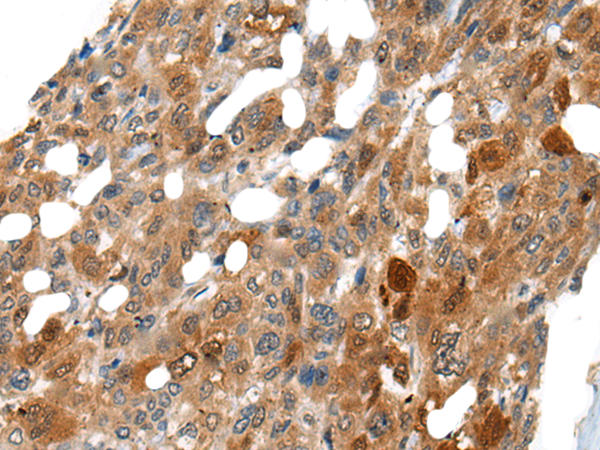

分类: 科研抗体货号: P06279别名:应用: WB,IHC反应种属: Human, Mouse, Rat

分类: 科研抗体货号: P06217别名: NEM7应用: WB,IHC反应种属: Human, Mouse, Rat

分类: 科研抗体货号: P06266别名: NCBP; Sto1; CBP80应用: WB,IHC反应种属: Human, Mouse, Rat

分类: 科研抗体货号: P06210别名:应用: WB,IHC反应种属: Human, Mouse, Rat

分类: 科研抗体货号: P06263别名: CML3; NACED; NAT8-LIKE应用: WB,IHC反应种属: Human, Mouse, Rat

分类: 科研抗体货号: P06205别名: CACC; GOB5; CACC1; CLCRG1; CaCC-1; hCLCA1; hCaCC-1应用: IHC反应种属: Human

分类: 科研抗体货号: P06262别名: DNAS1L2应用: IHC反应种属: Human, Mouse

分类: 科研抗体货号: P06202别名: AMY; CLAC; CLACP; CFEOM5; CLAC-P应用: WB,IHC反应种属: Human, Mouse

分类: 科研抗体货号: P06261别名: DCR2; CD264; TRUNDD; TRAILR4; TRAIL-R4应用: WB,IHC反应种属: Human